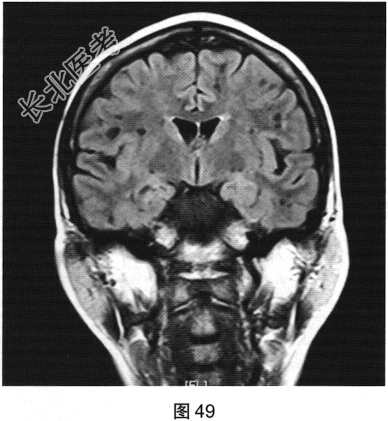

- 多项选择题2.[提示]患者行FLAIR、DWI及增强扫描,见图45~图54。该患者MRI影像的主要阳性表现有( )

C、双侧放射冠及半卵圆中心多发条状、圆形及卵圆形异常信号灶

E、病灶呈长T1、长T2信号,FLAIR为低信号,DWI为低信号,ADC为高信号